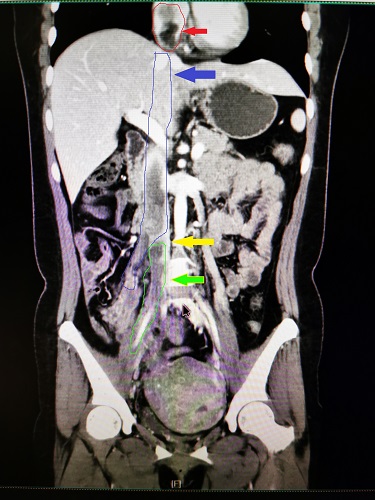

患者术前CT

主刀医生姚凯教授为患者制定了周密的手术方案,在狭小的腹盆腔中成功将下腔静脉及心脏内肿瘤通过下腔静脉切口完全取出,避免了二期手术或开胸手术,极大地减轻了患者痛苦及风险。值得一提的是,术中在髂静脉分叉部切开后,仅取出该段肿物,根据既往报道,肿物可能发生断裂并可能进入肺动脉引起生命危险,但根据台上患者生命体征仍旧平稳、心脏彩超示肿物未断裂并进入肺动脉,姚凯副教授准确判断肿物仍未断裂,再次温习CT、MRI后发现,与现有报道中的病例不同,肿物分别从髂静脉及右卵巢静脉内进入下腔静脉,遂灵活调整手术策略,在食道超声监测下,经下腔静脉-卵巢静脉交汇处切开,将心脏内肿物完整拖出心房,经下腔静脉完整取出肿物,成功完成手术。术后病人在ICU过渡一晚后即安返普通病房。在血管外科35病区医护团队的精心护理下,患者术后第7天顺利出院。